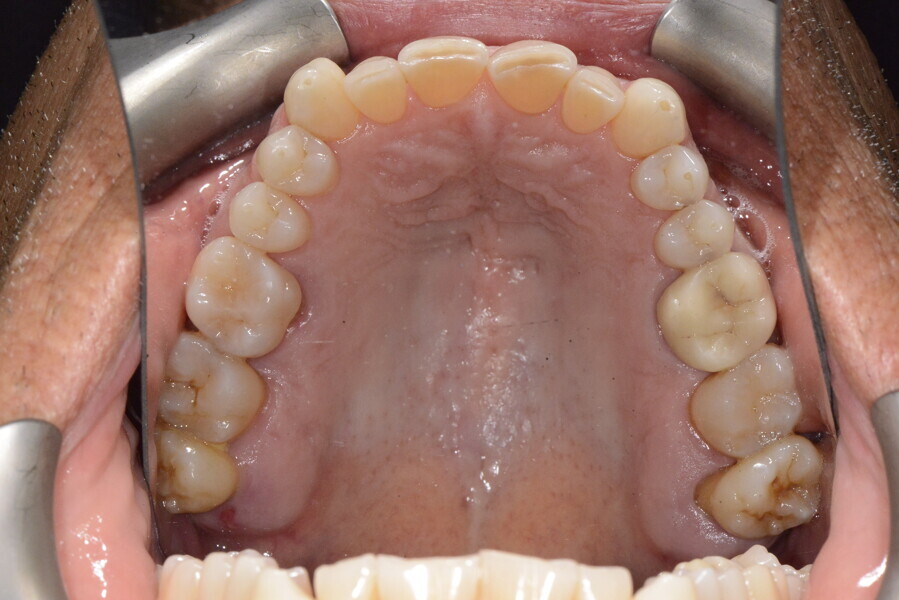

The 58-year-old patient wished to improve his oral aesthetics and function, complaining of mobility of the posterior teeth and wear of the anterior teeth. After data collection, a very complex situation was identified (Figs. 11–13):

1. severe periodontitis with poor prognosis of some teeth;

2. anterior crossbite;

3. severe wear mainly of the anterior teeth and compensatory eruption;38

4. atypical swallowing and lower posture of the tongue at rest;

5. masticatory dysfunction during the mastication test; and

6. no significant signs of temporomandibular disorder.